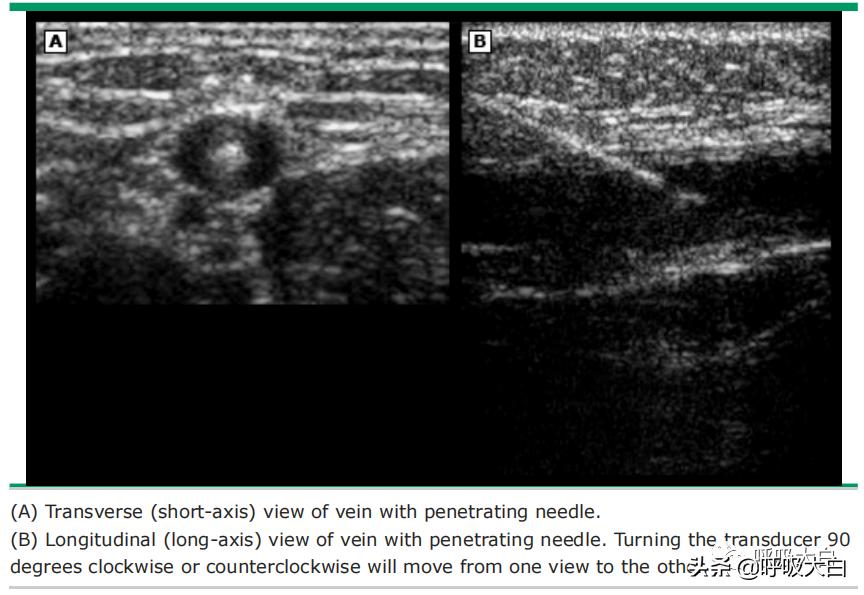

●为探头的外部包裹物涂抹无菌超声传导介质,如水溶性润滑剂。在超声屏幕(横切面)上识别股静脉并使其位于屏幕中央,也可采用纵切面图像,但要仔细区分动脉和静脉(影像 1)。

●将连接在注射器上的穿刺针(最好是强回声穿刺针)刺入皮肤,并朝静脉缓慢进针。

●如果横切面上难以看到针尖,则在组织中上下轻柔地摇动穿刺针以帮助识别穿刺针。在横切面上,调整超声束以聚焦在针尖上而不是针杆上很重要。未能这样做可导致不慎刺到更深层的结构。

●如果使用纵切面,可在超声监视器上直接观察穿刺针刺入静脉。在保持对注射器施加负压的同时,缓慢进针直至注射器内出现回血。虽然可能观察不到针尖,但超声监视器上可显示出血管的深度,应据此确定穿刺针的放置深度。